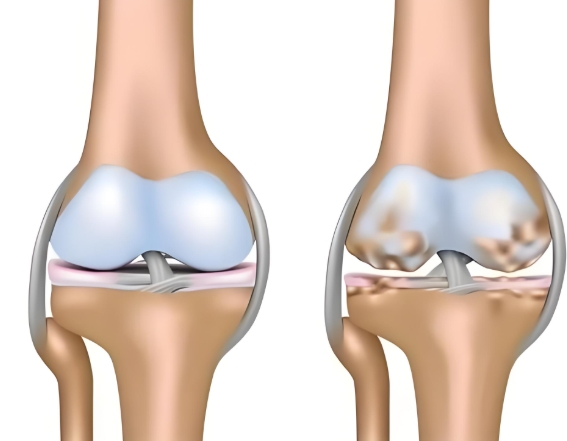

长期高油高糖、饮食不规律,很容易导致体重超标,而肥胖正是关节的 “隐形杀手”。多余的体重会让膝关节、髋关节等负重部位承受巨大压力,加速软骨磨损,久而久之,关节疼痛、僵硬、活动受限等问题接踵而至,大大增加骨关节炎的发病风险。而一旦患上骨关节炎是不可逆的,需要长期管理来延缓病情进展,氨糖就是临床常用,修复软骨、抑制损伤的优选。但它还有两种类型,到底盐酸和硫酸氨基葡萄糖有何不同?骨关节炎患者应该选哪个呢?